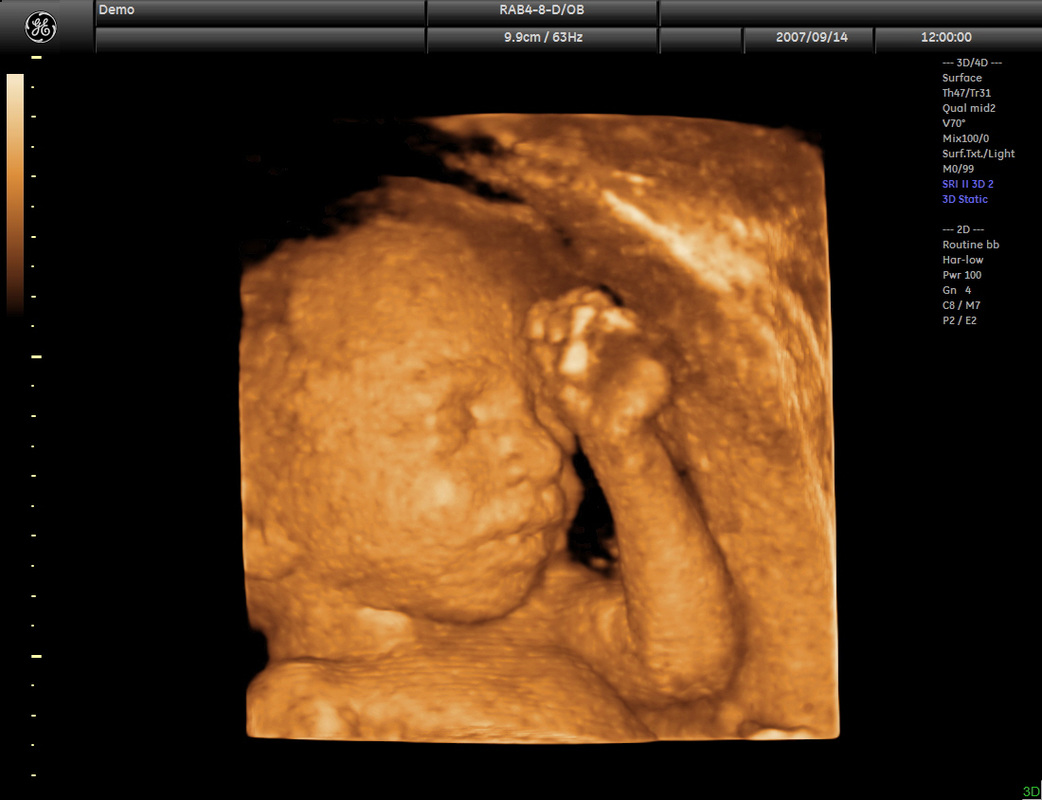

Gestation period of between 25-30 weeks is optimal for a great 3D/4D ultrasound scan and thus a crystal.

Scans can be performed earlier than this and we are able to get great results. The earlier in the pregnancy, the earlier the development of your child.

If performing before the 25 week period your baby may not have a developed a high fat layer and can appear skeletal in appearance.

This is fine and part of the natural part of the growth of you child.

To get really accurate example of your baby we advise between 25-30 weeks but we are happy to conduct scans before this.

See examples of the gestation's below to see where you fit!